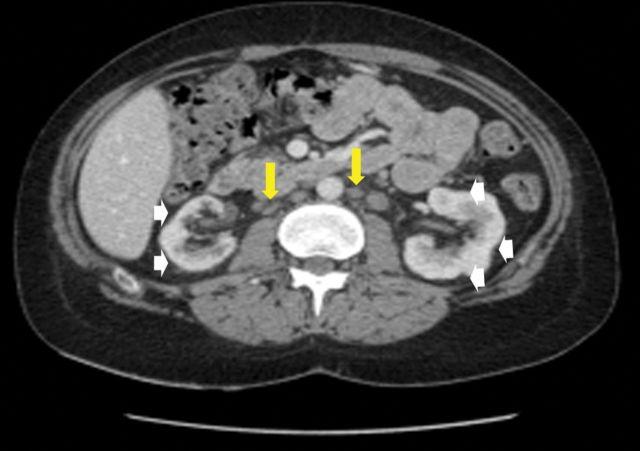

Renal sarcoidosis embraces a wide variety of clinical patterns. Renal vascular involvement has seldom been reported and usually in the setting of systemic vasculitis. We report the case of a 22-year-old patient in whom inaugural manifestation of renal sarcoidosis consisted of severe hypertension associated with bilateral perfusion defects and tumour-like nodules. In the setting of renal sarcoidosis, our case suggests that renin-dependant hypertension may arise from renal ischaemia as a result of extrinsic compression of kidney blood vessels due to severe granulomatous inflammation.

肾结节病有多种临床类型。肾血管受累鲜有报道,且通常发生在系统性血管炎的背景下。我们报告一例22岁患者,其肾结节病的首发表现为严重高血压,伴有双侧灌注缺损和肿瘤样结节。在肾结节病的情况下,我们的病例提示,肾素依赖性高血压可能源于严重肉芽肿性炎症导致肾血管外部受压引起的肾缺血。